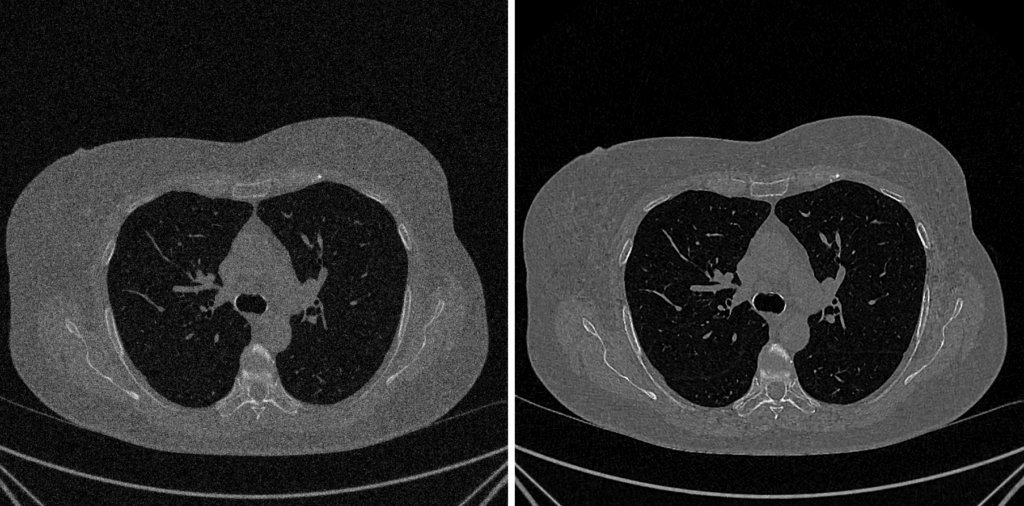

Equalizzazione Adattativa dell’Istogramma (CLAHE)

CLAHE rappresenta la soluzione “intelligente” e all’avanguardia per superare i limiti dell’equalizzazione globale, affermandosi come lo standard de-facto nell’imaging medicale.

Principio Fondamentale

A differenza dei metodi che analizzano l’istogramma complessivo, CLAHE opera localmente. Migliora il contrasto solo nelle aree necessarie, evitando al contempo l’amplificazione del rumore di fondo.

Processo Operativo (I 5 Passaggi)

- Suddivisione in Tessere (Tile Generation): L’immagine viene inizialmente suddivisa in una griglia di blocchi regionali di piccole dimensioni (le “tessere,” ad esempio 8×8).

- Calcolo degli Istogrammi Locali: Per ciascuna tessera viene calcolato un istogramma indipendente.

- Clipping dell’Istogramma (Il “CL” di CLAHE): Questa fase cruciale impone un “limite” (il Clip Limit). Qualsiasi livello di grigio (bin) che superi tale limite, spesso a causa della presenza di rumore, viene “tagliato.” L’eccesso risultante viene poi ridistribuito uniformemente sugli altri bin. Questo meccanismo previene efficacemente la sovra-amplificazione del rumore.

- Equalizzazione Adattiva: Viene applicata la classica equalizzazione (basata sulla funzione di distribuzione cumulativa – CDF) a ciascun istogramma locale che è stato “clippato.”

- Interpolazione per Fluidità: Per eliminare l’effetto visivo “a scacchiera” derivante dalla divisione in tessere, i valori finali dei pixel vengono calcolati tramite interpolazione bilineare tra le mappature delle tessere adiacenti, garantendo una transizione cromatica fluida e omogenea.